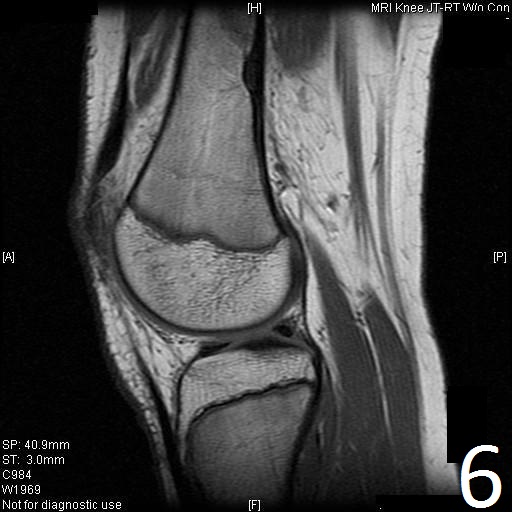

MRI

• Low- signal on T1 (Fig. 8)

Fig. 6

Fig. 7

Fig. 6-9: Sagittal T1 (Fig. 6) and T2 (Fig. 7) MRI of the knee demonstrates a fibrous cortical defect. Axial T1W (Fig. 8) and T2W (Fig. 9) show a heterogeneous lesion on distal femur, compatible with nonossifying fibroma.